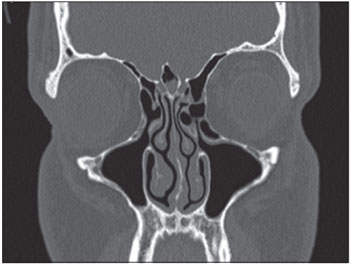

CASE STUDY #1A 57-year-old female patient sought advice from the Specialized Service in Otolaryngology in June 2008, complaining of a frontal headache that had been present for the last year. The patient reported previous drug treatments for sinusitis including azithromycin for 5 days, amoxicillin for 10 days, and a combination of amoxicillin and clavulanate potassium for 10 days. However, she always experienced recurrence and progressive worsening of her symptoms. Examination with video-endoscopy showed hypertrophy of the lower and middle turbinates bilaterally associated with septal deviation in the left nasal cavity. A computed tomography (CT) scan of the paranasal sinuses and nasal cavity in the axial, coronal, and sagittal planes with a bone window of 2500-3500 rads was requested, which identified pneumatization of the crista galli with mild mucosal thickening in the interior (Figure 1). This finding indicated endoscopic surgery through the transseptal approach in the left nasal cavity for drainage and cleaning of the pneumatized crista galli (Figure 2).

Figure 1. Preoperative coronal section CT scan showing crista galli pneumatization with mucosal thickening.

CASE STUDY #2A 35-year-old female patient sought advice from the Specialized Service in Otolaryngology in August 2010, complaining of a localized headache, cacosmia, and nasal obstruction with progressive worsening of her symptoms during the previous 6 months. Her symptoms had remained after drug treatment with amoxicillin and clavulanate potassium for 10 days. Video-endoscopy showed a deviated septum and inferior turbinate hypertrophy. A CT scan of the paranasal sinuses and nasal cavity in the axial, coronal, and sagittal planes with a bone window of 2500-3500 rads was requested, which identified pneumatization of the crista galli apophysis with signs of mucosal thickening and obliteration interiorly. We introduced antibiotic treatment (levofloxacin at a dose of 500 mg/day) for 14 days, corticosteroids (prednisone at a dose of 40 mg/day) for 7 days, and symptomatic analgesia. The patient's symptoms improved temporarily, but 5 days after treatment with antibiotics was stopped, recurrence of her symptoms occurred. A second CT scan of the paranasal sinuses and nasal cavity showed the maintenance of mucosal thickening and obliteration within the crista galli (Figure 3). Endoscopic surgery by a transseptal approach through the right nostril was indicated for drainage and cleaning of the pneumatized crista galli (Figures 4-7).

Figure 3. Coronal CT section showing mucosal thickening and obliteration of the pneumatized crista galli.

CASE STUDY #3A 31-year-old male patient sought advice from the Specialized Service in Otolaryngology in April 2012, with the complaint of chronic nasal obstruction that had been present since childhood and was associated with the symptoms of congestion, rhinorrhea, and facial pain localized in the frontal region for the last 3 months. He had shown no improvement after 2 previous episodes of treatment with antibiotics (levofloxin and amoxicillin lasting 10 days and 14 days, respectively). He also reported a history of adenoidectomy surgery prior to the age of 5. Video-endoscopic examination identified the presence of septal deviation in the left nasal cavity associated with mild inferior and right middle turbinate hypertrophy as well as hypertrophy of lymphoid tissue in the nasopharynx. A sinus and nasal cavity CT scan in the axial, coronal, and sagittal planes was requested, which identified septal deviation with bone spur formation, prominence of the soft parts of the cavum, and pneumatization of the crista galli with significant mucosal thickening and fluid present within (Figure 8). The patient underwent surgical resection of the lymphoid tissue present in the nasopharynx and transseptal endoscopic drainage of the pneumatized crista galli.

Figure 8. Coronal CT section showing mucosal thickening and fluid within the pneumatized crista galli.